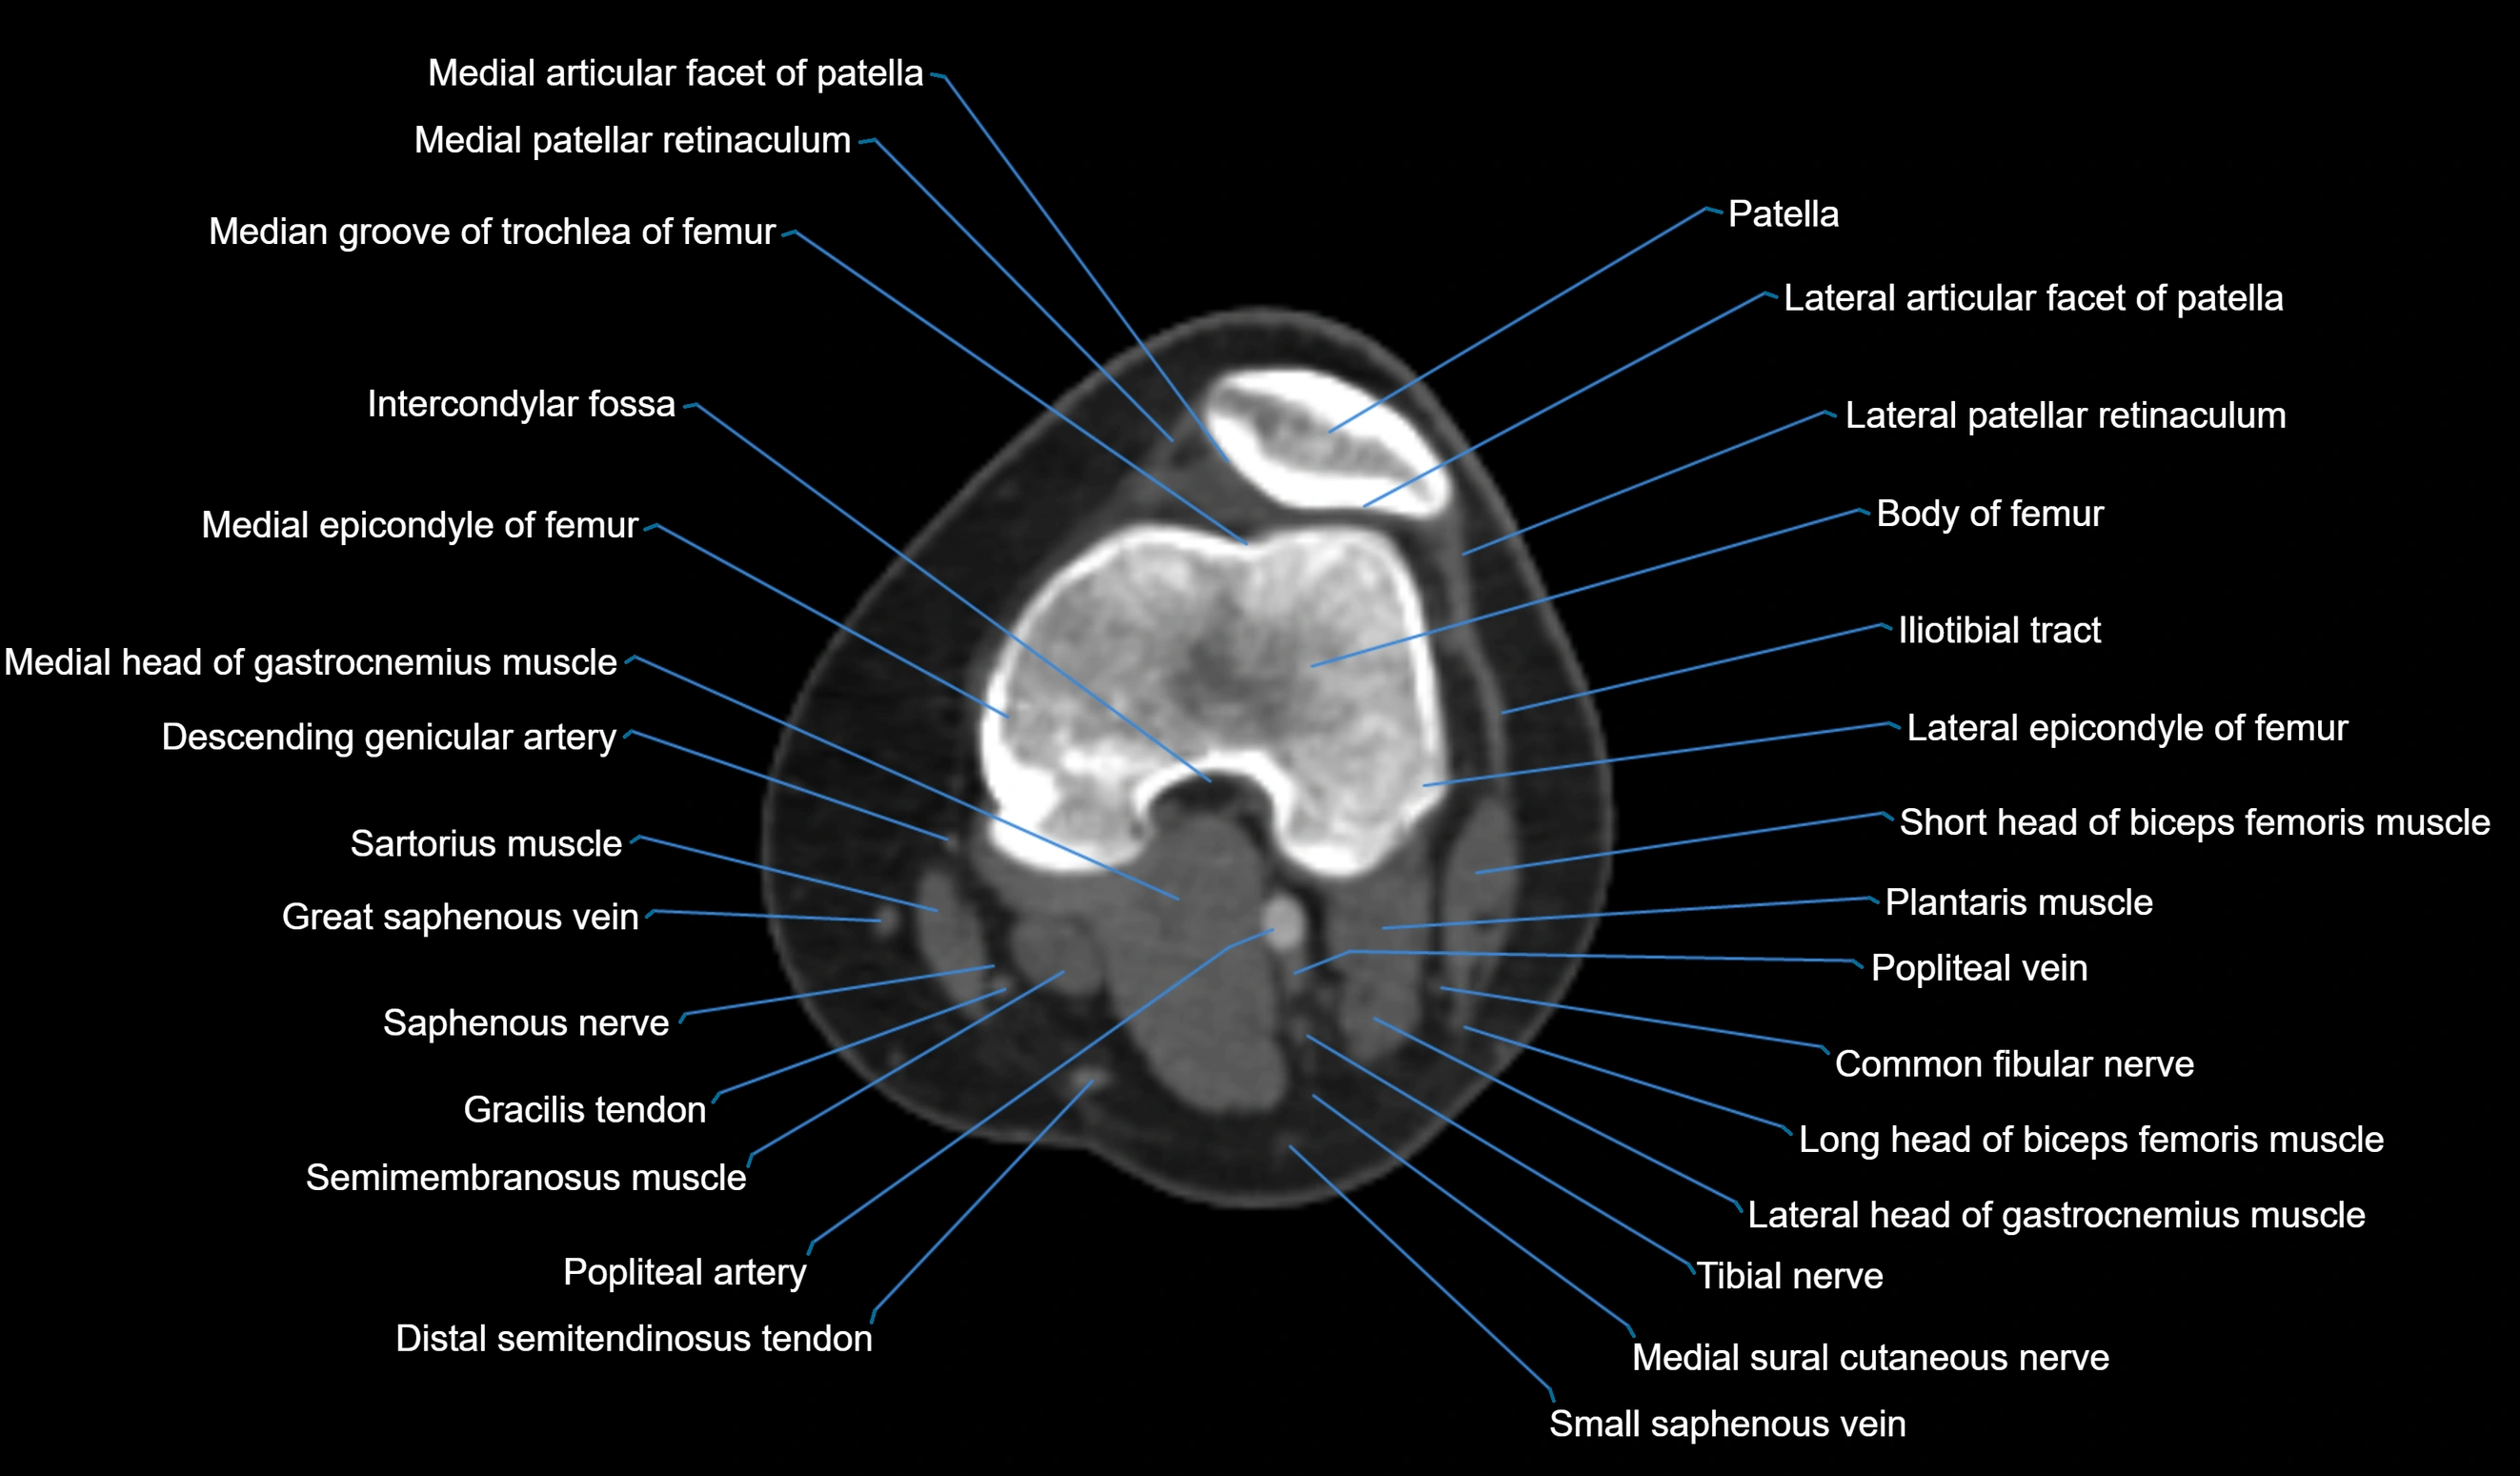

- Body of femur

- Lateral articular facet of patella

- Lateral epicondyle of femur

- Lateral head of gastrocnemius muscle

- Lateral patellar retinaculum

- Medial articular facet of patella

- Medial epicondyle of femur

- Medial head of gastrocnemius muscle

- Patella

- Plantaris muscle

- Popliteal vein

- Saphenous nerve

- Sartorius muscle

- Semimembranosus muscle

- Small saphenous vein

- Tibial nerve